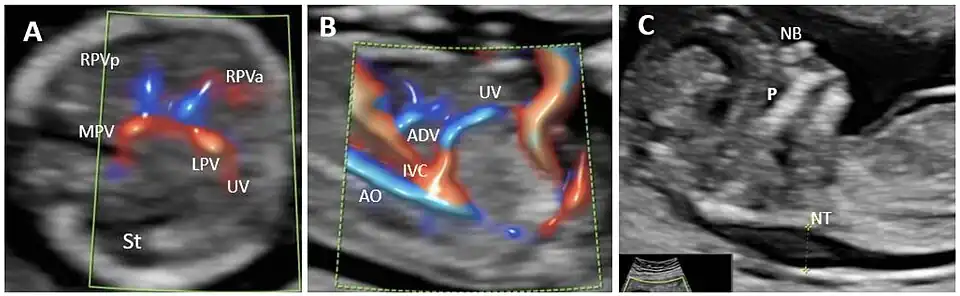

Agenesis of ductus venosus (ADV) in a first trimester case with umbilical vein drainage into inferior vena cava (IVC) and increased nuchal translucency. (A): Transverse plane of the FT fetal abdomen, with high-definition directional power Doppler applied. An ”H”-shaped variant of the intrahepatic portal veins connection is identified; (B): high-definition directional power Doppler in the sagittal plane of the fetal abdomen (same case) showing ADV with umbilical vein drainage into the inferior vena cava; (C): mid-sagittal view of the fetal face with the measurement of the thickened NT. MPV main portal vein, St stomach, LPV left portal vein, UV umbilical vein, RPVa anterior branch of right portal vein, RPVp posterior branch of right portal vein, Ao aorta, IVC inferior vena cava, ADV ductus venosus agenesis, P palate, NB nasal bone, NT nuchal translucency.